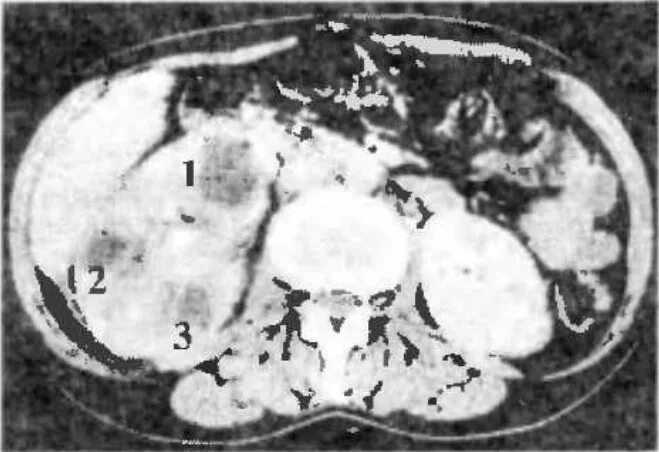

Пиелонефрит кт